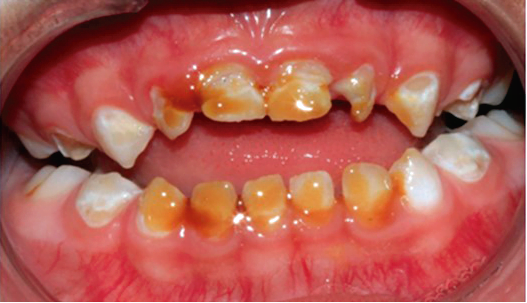

Se llevó a cabo la exploración extraoral y se logró apreciar una ligera asimetría facial, en las fotografías de perfil se ve la implantación de la oreja por debajo de lo normal (figura 1). Al hacer la exploración intraoral se encontraron sobre la superficie de todos los dientes manchas de color amarillento con descalcificaciones y lesiones cavitadas, al complementarse con la historia clínica y antecedentes patológicos, se determinó el diagnóstico de hipoplasia del esmalte generalizada (figura 2).

Figura 2. Examen clínico extraoral.